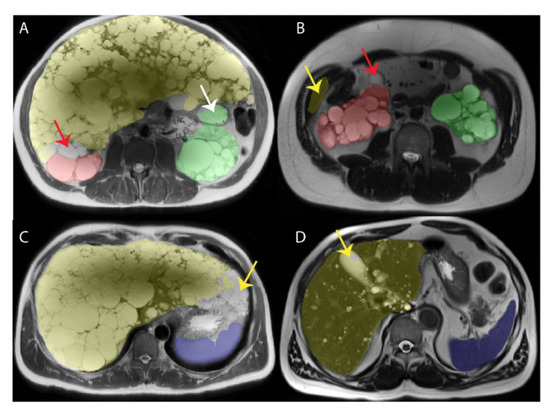

- Riyahi, S.; Dev, H.; Blumenfeld, J.D.; Rennert, H.; Yin, X.; Attari, H.; Barash, I.; Chicos, I.; Bobb, W.; Donahue, S.; et al. Hemorrhagic Cysts and Other MR Biomarkers for Predicting Renal Dysfunction Progression in Autosomal Dominant Polycystic Kidney Disease. J. Magn. Reson. Imaging 2021, 53, 564–576. [Google Scholar] [CrossRef] [PubMed]